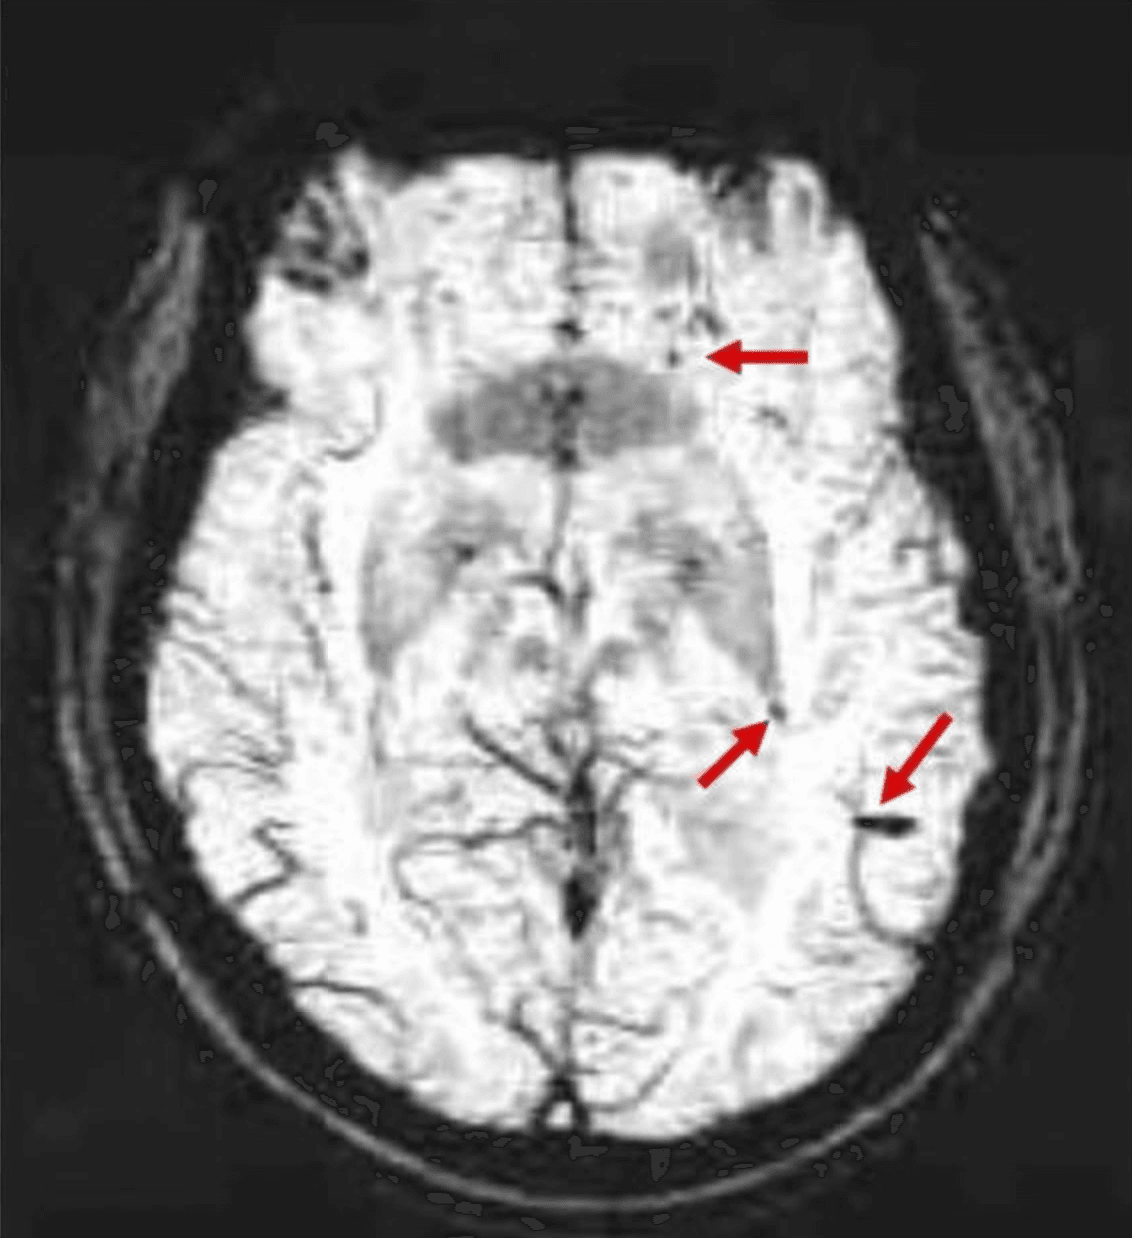

Complete blood count shows white blood cell count 10,800/μL with absolute eosinophil count 980/μL (9% of differential). Hemoglobin and platelets are normal. Comprehensive metabolic panel is unremarkable. MRI of the brain with and without gadolinium shows mild leptomeningeal enhancement without mass lesions, cerebral edema, or hydrocephalus. Lumbar puncture reveals an opening pressure of 31 cm H₂O. CSF analysis: WBC 310 cells/μL (42% eosinophils, 38% lymphocytes, 20% monocytes), protein 92 mg/dL, glucose 44 mg/dL with a serum glucose of 96 mg/dL. No organisms are seen on Gram stain. CSF bacterial cultures are pending. CSF cryptococcal antigen is negative.

Susceptibility-weighted MRI: multiple microbleeds (arrows) over bilateral cerebral and cerebellar hemispheres. Adapted from Graeff-Teixeira et al. PLOS Neglected Tropical Diseases, 2009 (PMID: 29187276).